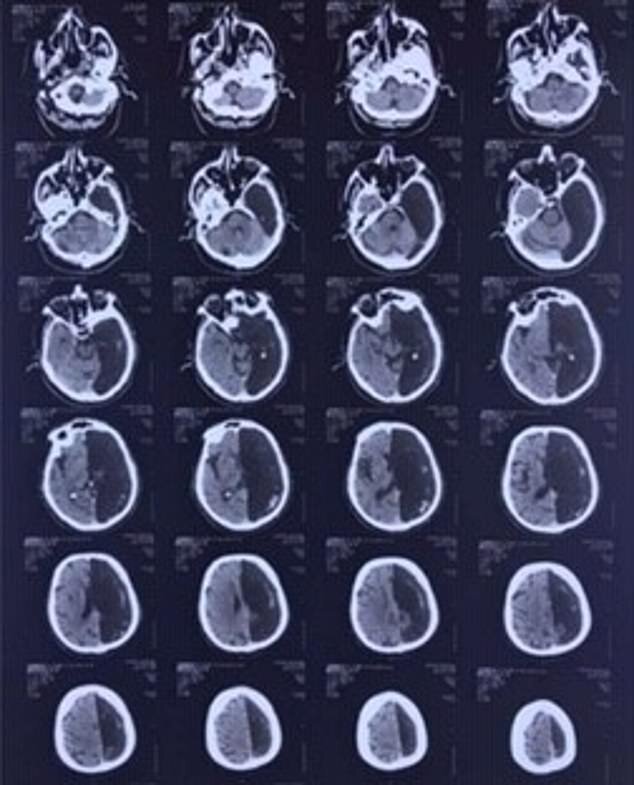

هنگامیکه این مرد به دلیل حمله قلبی به بیمارستان منتقل شد، پزشکان با انجام سی تی اسکن متوجه شدند نیمی از مغز او وجود ندارد.

دکتر مارینا آنیکینا که درباره این پرونده پزشکی تحقیق می کند در این باره می گوید: این مرد به دلیل حمله ایسکمی به کلینیکی در جنوب مسکو مراجعه می کند. در این شرایط گردش خون در مغز دچار اختلال می شود. این وضعیت با سکته متفاوت است. همچنین این مرد برای حرکت دادن یک بازو و یک پا مشکل داشت. رادیولوژیست ها توموگرافی رایانشی از مغز او انجام دادند و در کمال تعجب متوجه شدند نیمی از مغز این مرد که حمله ایسکمی در آن اتفاق می افتد، اصلاً وجود ندارد. در بخشی از جمجمه که باید قسمت چپ مغز وجود داشته باشد، یک حفره سیاه وجود دارد.